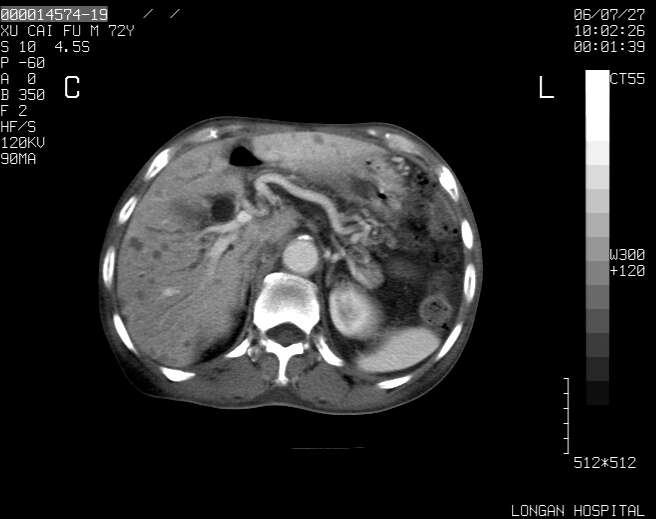

以下是引用winter在2006-7-30 20:14:00的发言:[br]1、考虑胆囊癌伴胆道侵犯并高位胆道梗阻、肝内多发转移、腹膜后淋巴结转移。[br]2、右肾轻度积水。[br]3、老人家72岁了胰腺头体尾部均较饱满,不过未见密度异常及其他异常征象。[br]4、腹水。

以下是引用jiajie在2006-7-31 7:10:00的发言:[br]考虑肝转移瘤,腹膜后淋巴结增大。[br]胃癌不能除外,建议胃镜检查。